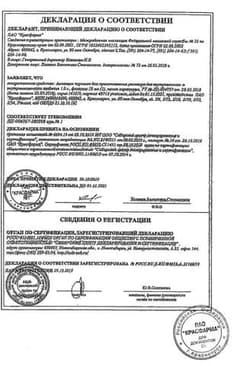

Сертификаты